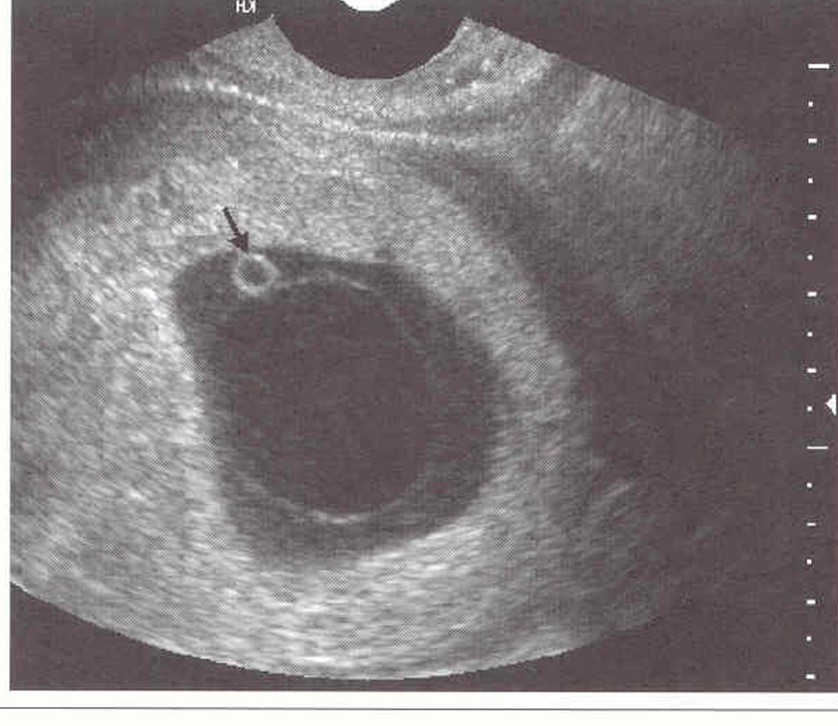

NOT BLACK ARROW

dark ring around gest sac

choronic cavity

darkest circle

amniotic cavity

thin white curved line at top

amniotic membraine

blastocele

blastocyst

blastomere

1 – decidua capsularis

2- Chorionic membrane

3 – amniotic cavity

4 – chorionic cavity

5- yolk sac

6 – decidua basalis